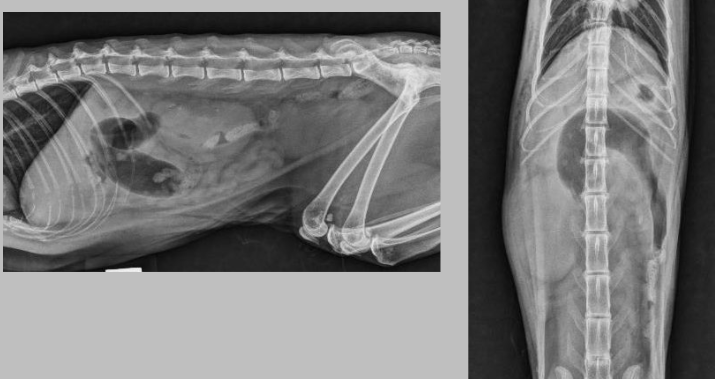

Q

the kidneys, both, are enlarged. this is lymphoma

what is going on here?

A

one of the kidneys appears large and absnormally shaped, very circular, and there are small white opacities which are probably stones. this is hydronephrosis secondary to obstructive uropathy